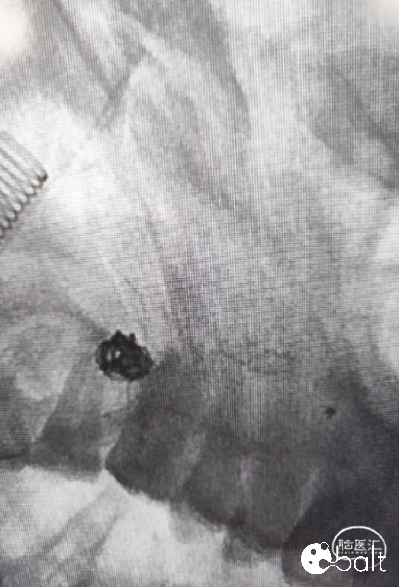

术后影像

术后工作位手推造影、术后正位造影。

术后工作位手推造影

术后造影显示动脉瘤致密栓塞,各分支血管血流通畅。